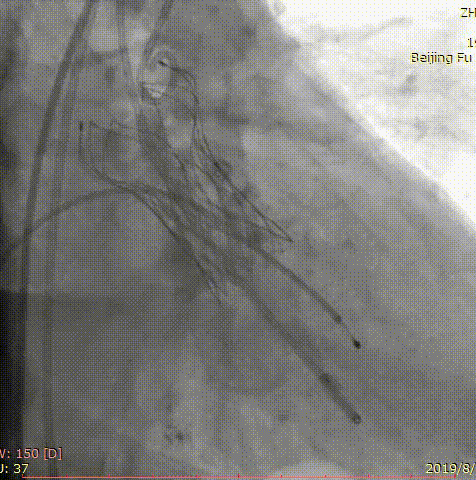

第三位患者是一位84岁女性,因间断头晕伴气短2年,加重1年入院,超声心动图提示主动脉瓣重度狭窄,左室壁肥厚,节段性室壁运动减低,主动脉瓣平均跨瓣压差91mmHg,收缩期流速 m/s,瓣口面积 0.6cm2。患者合并房颤、慢性肾功能不全、贫血。完善CT检查,测得主动脉瓣环 21*25mm,周长71.3mm,面积399.2mm2,患者三叶瓣,钙化分布较均匀,结合瓣上多平面分析方法,选择经左侧股动脉,应用微创心通 20*40mm敖广球囊预扩张,并成功植入Vitaflow 24mm主动脉瓣膜。术后超声提示收缩期流速1.7m/s,较术前明显下降。

术前影像